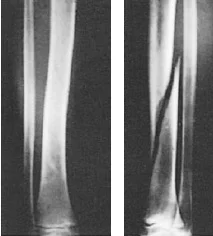

Fracture Pattern and Mechanism of Force

- Fracture pattern suggests mechanism of force

- Spiral: (twisting)

- Short oblique: (compression)

- Wedge: (compression + bending)

- Transverse: (angulation) (avulsion)